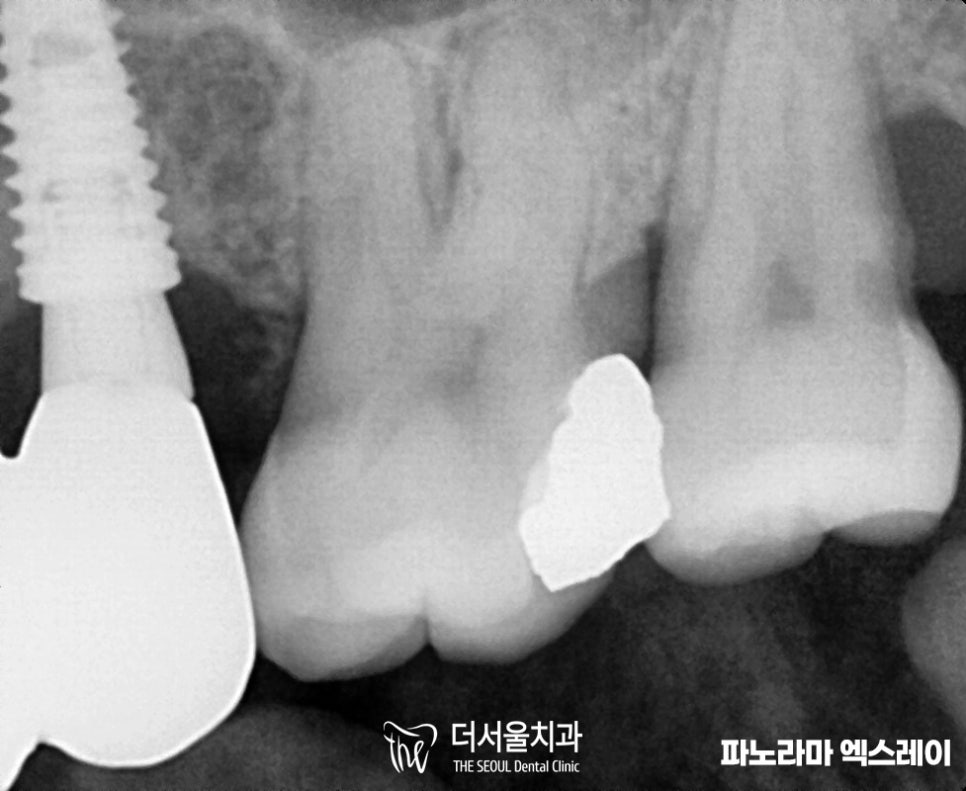

해당 환자분께 26, 27번 어금니 치아 는

꼭 충치 해결해야 된다

그렇게 말씀드렸었는데요.

결국 방치하셨던 결과는

사진에서 보여지듯

시커멓게 변해버린 이가 보입니다.

현재 아말감으로 떼워놓았기에

얼마나 썩었는지 알기 어렵지만,

주변으로 시커멓게 변한 부분을 보면

꽤 심각하다는 것을 알 수 있죠.

파노라마 엑스레이 촬영으로는

확인이 어려웠습니다.